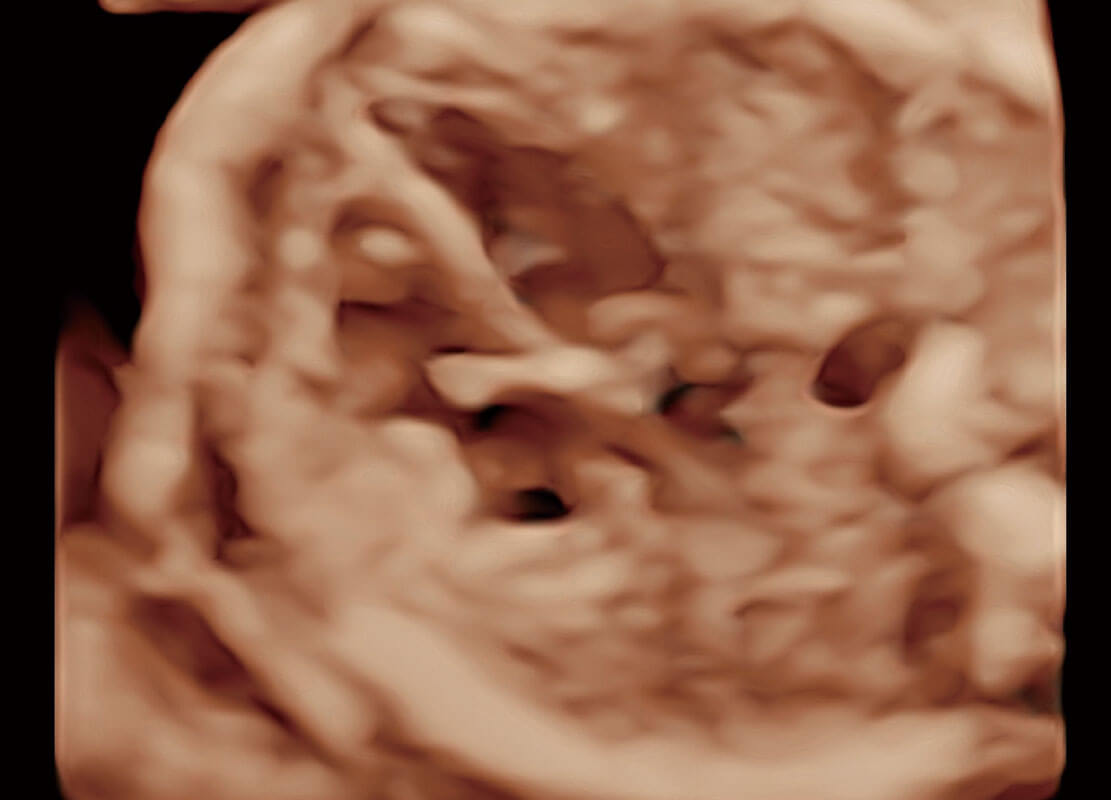

P60在胎儿早孕期超声筛查中为您带来优异的图像质量。

早孕-胎心

高分辨率容积成像-早孕胎儿

胎儿体循环

光影成像-孕囊